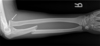

100

Describe this fracture?

MONTEGGIA - Fracture of junction of proximal & middle thirds of ulna w/ anterior dislocation of radial head - PIN injury (weak thumb or finger ext) - FOOSH with forced pronation or direct blow to ulna - Cast in supination in KIDS